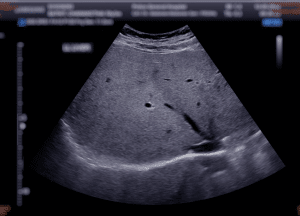

Figure 1: Ultrasound upper abdomen showing liver

Abdominal ultrasonography is the most employed initial imaging tool in assessment of liver in cirrhosis because of its availability, affordability and free from radiation exposure.